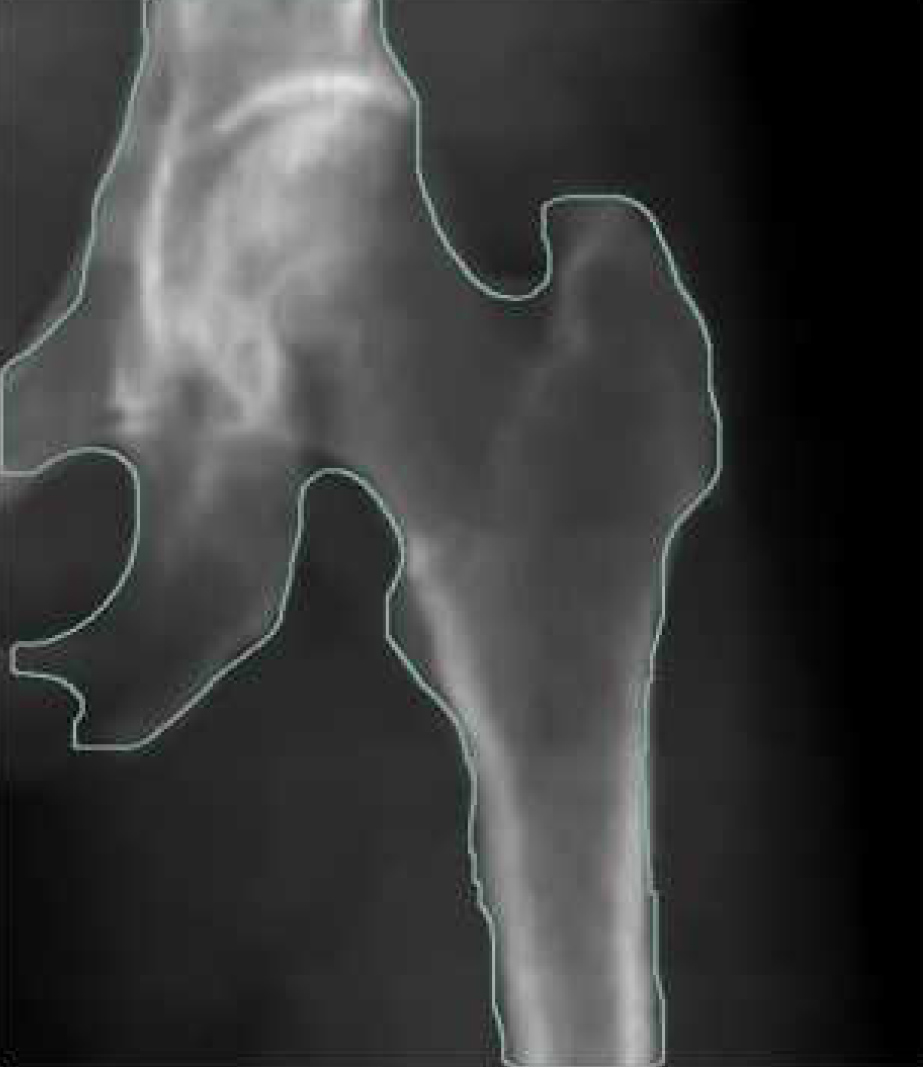

Scan site Spine, Femur, Forearm

نام نواحی مورد اسکن: Femur-Forearm-Spine

Femur: Neck,Wards,Grand Troachanter, Total

مشخص کردن مناطق نواحی اسکن ROI بصورت اتوماتیک